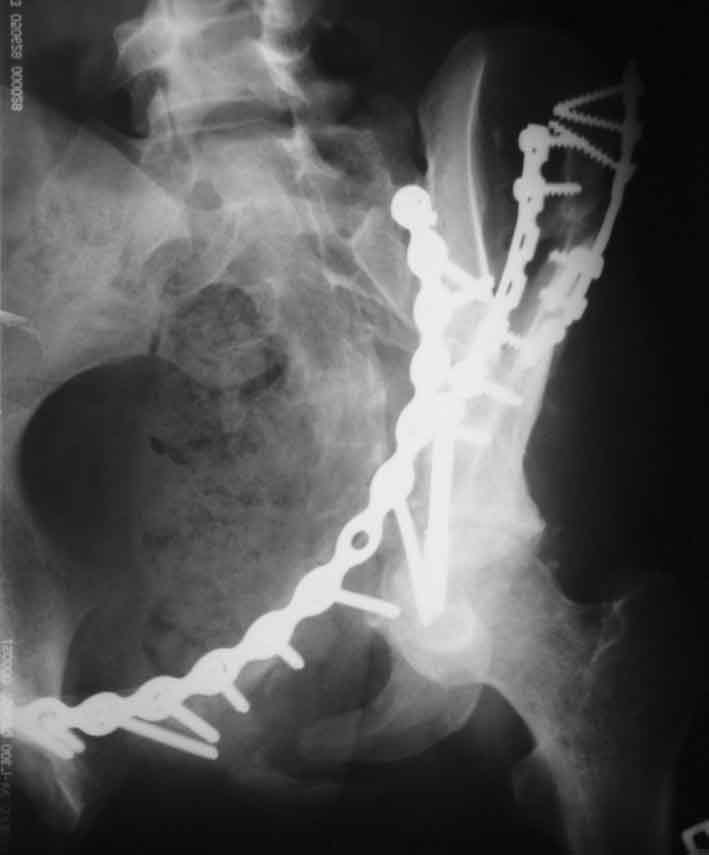

Рентгенограммы после операции

inlet

A>РО - картина не очень, есть видимость винтов во впадине

По всей видимости, вы имеете в виду канюлированный винт, который проецируется на вертлужной впадине. Та вот, он проведен не через лонную, а седалищную кость. Вертлужная впадина абсолютно интактна. Это хорошо видно на проекции inlet.